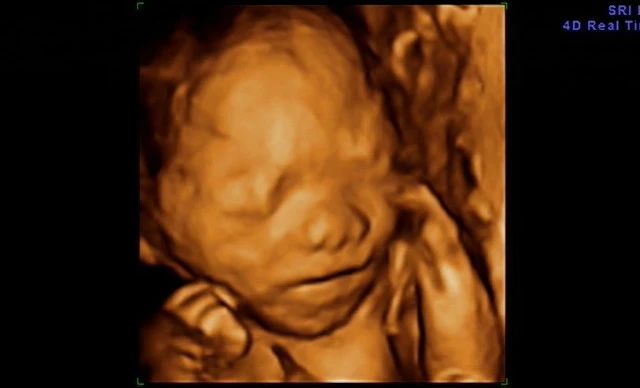

大连新百佳妇儿医院四维彩超预约,四维和普通彩超有什么区别?大连新百佳妇儿医院超声科医生李萍带您了解,近日抖音上一个视频火了。一位孕妈妈在做超声影像(四维彩超)的时候胎宝宝不配合,她又爬楼梯又吃冰淇淋,折腾大半天才通过。虽然宝宝很健康,但孕妈妈看过宝宝的四维照后却哭得梨花带雨:”太丑了,没见过那么丑的。还没出生,就被亲妈嫌弃成这样,求宝宝心理阴暗面积。

▲图片已经客户授权

大连新百佳妇儿医院医生表示,说起超声影像(四维彩超),很多孕妈妈都很期待与宝宝的第一次会面,渴望看到自家宝贝的”盛世美颜“。可是屏幕里这个塌塌鼻、大嘴巴、坑坑洼洼的”小泥人“简直让孕妈们的玻璃心碎成了渣~>>>在线客服

超声影像(四维彩超)的立体图像能更清楚地看到宝宝的五官,甚至还会有吃小手、打哈欠等淘气的模样,满足了孕妈妈想提前知道宝宝样子的好奇心,但是很多孕妈妈并不清楚,超声影像(四维彩超)和B超究竟有什么区别。

大连新百佳妇儿医院医生李萍提醒,超声影像(四维彩超)需建立在二维超声切面基础上,采用四维成像技术,检查结果更为直观,立体,针对胎儿的生长发育做筛查,如发现唇裂、脊柱裂,大脑、肾、心脏、骨骼发育不良等情况,为早期诊断胎儿先天性体表缺陷和先天性心脏疾病提供准确的科学依据。